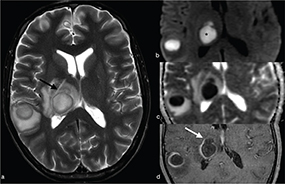

Cerebral toxoplasmosis is typical of immunocompromised patients. MRI shows multiple lesions in different stages of evolution typically located in the subcortical and periventricular white matter, in the basal ganglia and thalami. In particular, two signs are recognised as typical of toxoplasmosis: the “concentric” target sign (concentric alternating hypointense and hyperintense rims in T2w images), and the “eccentric” target sign (peripheral rim of enhancement and focal lateral eccentric enhancing nodule on T1w post-contrast) (Figure 16). On DWI, the centre of the toxoplasma abscess is seen to have ADC values higher than in pyogenic abscesses.22

FIG 16. Multiple Toxoplasma gondii Abscesses in a 45-Year-Old Immunocompromised Woman. T2w (a), T1+Gd (b, f), rCBV map (c), DWI (d) and ADC map (e). Multiple supratentorial brain abscesses in various stages of development with enhancing asymmetric nodules after Gd-injection (“eccentric target sign”) (arrows) can be observed (b, f). Note also the concentric alternating zones of hypo- and hyperintensities on T2w: “concentric target sign” (circle in a). Toxoplasma gondii abscesses typically do not show a core of restricted diffusion on DWI (asterisk in d) while low ADC values may be seen in the capsule (e).